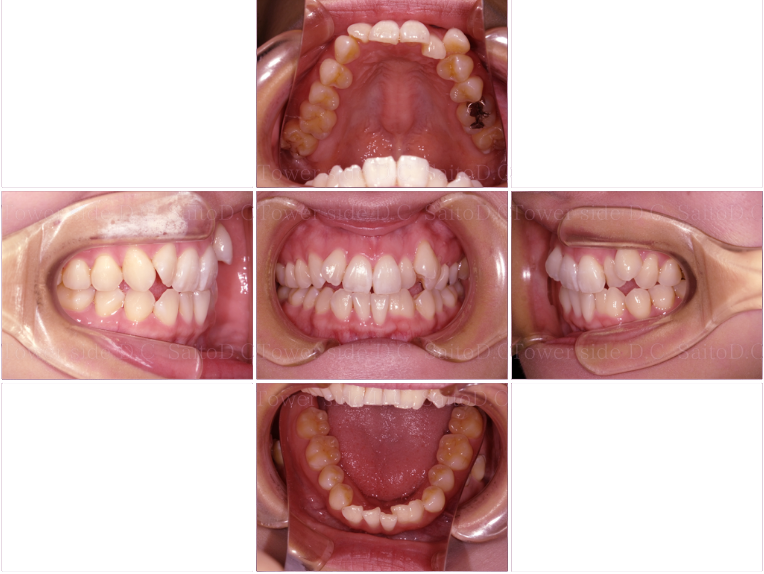

症例(施術前)

症例(施術後)

主訴 上前歯が出ている、上下前歯がガタガタが気になる

状況

• 上顎前歯前突

• 下顎前歯叢生

• 過蓋咬合

治療費 968,000円(税込)(自由診療)

治療期間 2年3ヶ月

治療内容 14.24を抜歯し、ワイヤー部分矯正で抜歯スペースを閉鎖後、マウスピース矯正を使用して臼歯部や前歯の方向を正しい向きに改善。歯並び、過蓋咬合、臼歯部噛み合わせは改善されその後保定装置(リテーナー)を使用し安定している。